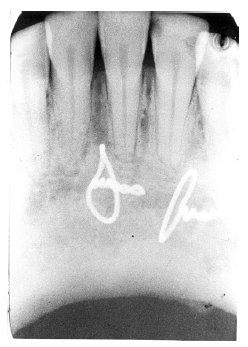

A crown fracture can also affect the tooth root, appearing as a radiolucent line across or with the tooth’s long axis. Be careful not to mistake the artifact of a fingernail crimp as a fracture! Figure 22 is a radiographic image of a fractured tooth. A fingernail crimp would be very similar, though possibly somewhat more broad and radiolucent (Figure 23).

Figure 22 - Fractured Root

Figure 22

Figure 23 - Fingernail Crimp on Radiographic image

Figure 23